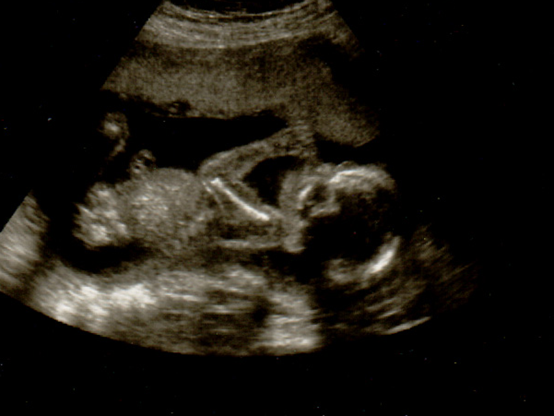

Αυτό το είδος θηλασμού θεωρείται απόλυτα φυσιολογικό σε βρέφη και παιδιά μικρής ηλικίας, καθώς είναι μια συνήθεια που προσφέρει αίσθηση ασφάλειας και θαλπωρής. Είναι μια αυτόματη λειτουργία, η οποία ικανοποιεί το πρωταρχικό ένστικτο της αυτοσυντήρησης, δηλαδή της λήψης τροφής και της θρέψης. Είναι χαρακτηριστική η εικόνα του υπερηχογραφήματος, όπου φαίνεται το έμβρυο να θηλάζει τον αντίχειρα ή κάποιο άλλο δάχτυλο, πριν ακόμη γεννηθεί!